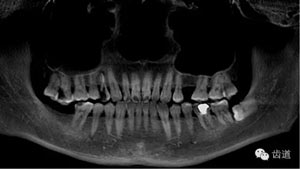

好的開始就是成功的一半。通過CBCT了解根管的位置,形態(tài),方向。

檢查顯示:近頰及腭根充填恰填,遠(yuǎn)頰根管內(nèi)有少許充填物影像。根尖明顯低密度影像。

診斷:慢性根尖周炎。